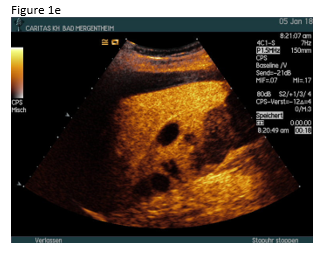

A 49 year old patient was admitted to the hospital for sepsis and shock of unknown origin. The patient presented with signs of sepsis and hemodynamic instability that justified an urgent approach including complex intensive care and intubation. Bedside ultrasound (US) found ascites and an abscess in the right liver lobe (9 cm) (Figure 1a). The patient was treated with broad-spectrum antibiotics and puncture and drainage of the abscess (Figures 1 a-c and 2 a-b). In addition, a biopsy was taken from the periphery of the lesion. A few days after the removal of the drainage the patient presented with a progressive elevation of liver enzymes. US revealed a cystic lesion measuring 30 mm that was proximal to the drained abscess (Figure 1a). Color Doppler Imaging (CDI) showed arterial flow inside the lesion, and contrast enhanced ultrasound (CEUS) showed early arterial enhancement and turbulent flow with a “to-and-fro” sign, suggestive of a pseudoaneurysm (Figure 1b). There was also a heterogeneously vascularized lesion with enhancing septae in the surrounding liver parenchyma (Figure 1c) . A few days later the patient presented with tachycardia and a drop of hemoglobin from 10 g/dl to 7 g/dl. US revealed spontaneous thrombosis of the pseudoaneurysm (Figure 1d) with intra - and perihepatic hemorrhage (Figure 1e).

Phlegmonous inflammation and abscess formations show variable and sometimes confusing US B-mode findings, which may change over time. The surrounding hypervascularitiy of abscesses may support the development of pseudoaneurysm after puncture and drainage in a few patients. On B-mode US pseudoaneurysms may appear like a cystic tumor, therefore CDI should be preferred as the primary screening technique for detection of vascular complications. The swirling colour pattern of the flow within the pseudoaneurysm that mimicks the "yin-yang" symbol (so called “to-and-fro” pattern) and the presence of high velocity are characteristic features of these lesions [(1-3)].

Contrast enhanced imaging techniques including CEUS and CT are used to confirm the sonographic findings or when the US evaluation is inconclusive [4-9]. CEUS has several advantages compared to CT, such as no radiation exposure, low cost and absence of nephrotoxicity [3].